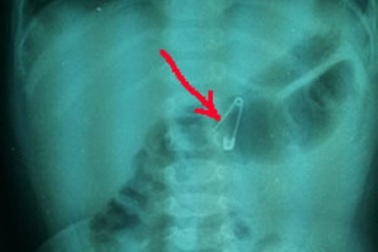

Mẹ sơ ý, bé 6 tháng tuổi nuốt kim băngMở kim băng áo cho con nhưng người mẹ sơ ý để trên giường. Bé gái 6 tháng tuổi nhặt cây kim cho vào miệng nuốt chửng.